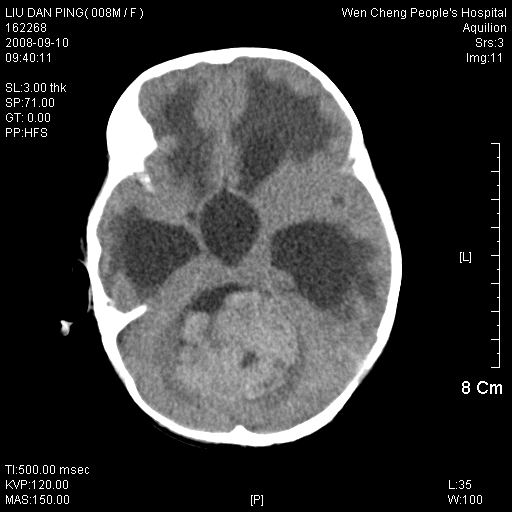

以下是引用卜一在2008-9-10 16:21:00的发言:[br]髓母细胞瘤伴梗阻性脑积水!支持![br]髓母细胞瘤特点:—般直径大于3.5cm,位于后颅凹中线之小脑蚓部。累及上蚓部的肿瘤延伸到小脑幕切迹之上,ct平扫肿瘤多呈均匀一致的高或等密度病灶,增强检查呈均匀一致的强化。病灶中有小坏死时,平扫亦可呈不均匀之混杂密度,注药后有增强。[br]

以下是引用zjzjr在2008-9-10 15:09:00的发言:[br]髓母细胞瘤伴梗阻性脑积水.